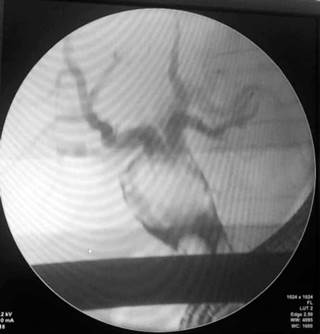

Se solicitó una valoración por radiología intervencionista, en la que se realizó embolización con Onix de pequeñas ramas de la arteria hepática derecha. La paciente continuó con sangrado, asociado con hipotensión y requerimiento de soporte vasopresor, por lo que fue llevada a nueva arteriografía urgente del tronco celíaco, y supraselectiva de arteria hepática derecha con intento de embolización del pseudoaneurisma hepático, el cual no fue exitoso. Debido a este resultado, se realizó una embolización percutánea del pseudoaneurisma, con evidencia fluoroscópica posterior de la corrección del mismo, sin complicaciones. La paciente presentó una adecuada evolución sin sangrado ni anemización y sin requerir intervenciones adicionales.